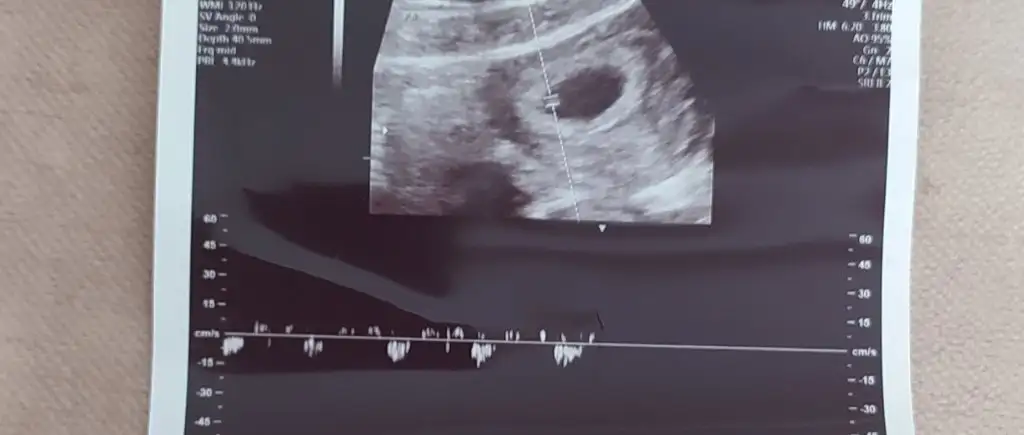

ya bir de cinsiyeti belli olan arkadaşlar kalp atışını kaç duymuştunuz hatırlıyor musunuz ? bazen kalp atışı da belli ediyor diyorlar

benim ilk haftalarda 130 du yanlış hatırlamıyosam cinsiyeti erkek

135 altı erkek 140 üstü kız diyorlar genelde. o zaman buna göre senin ki tutmuş :)

benim ki yine arada kaldı ya doktor bana 140 civarları demişti adhasdkaslja ay yok ben bu çocuğun cinsiyetini öğrenemicem hahahaha

Ben ona çok güvenmiyorum canım yaa, çünkü kalp atışını ne zaman duyduğuna göre değişir o.

Ben 5+4’te duydum, 89’du mesela.